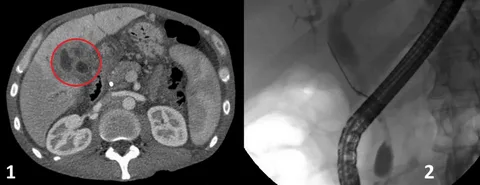

Cholangiocarcinoma, commonly known as bile duct cancer, is a rare but destructive form of cancer that develops in the bile duct. Initial diagnoses and specialized treatments are vital for handling this serious condition effectively.

Advanced diagnosis techniques are adopted, and the best possible treatment is opted out according to the condition and stage of the tumor, but most treatments include removing the bile duct or affected part.